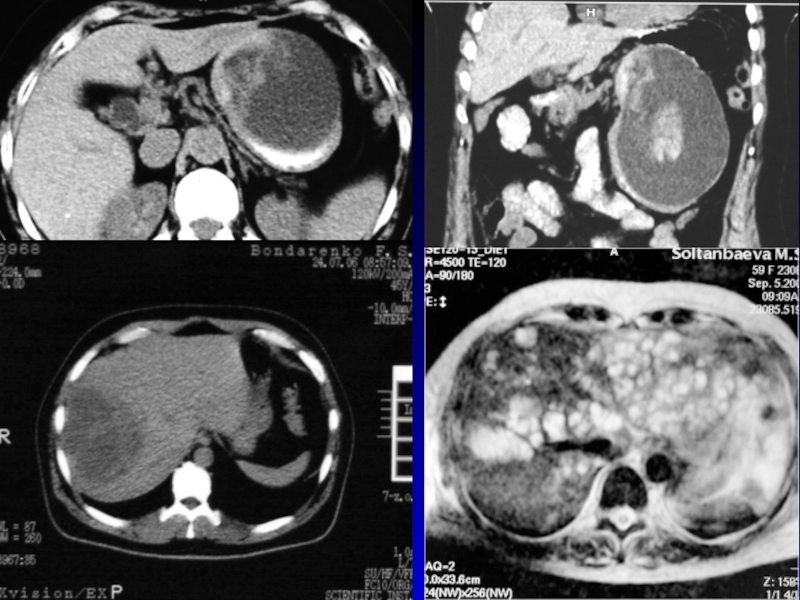

Слайд 20АБСЦЕСС

Ограниченное скопление гноя в различных тканях или органах, окруженное пиогенной

капсулой

Возбудитель – чаще стафилококк, анаэробные микроорганизмы

Проникновение в организм – через

повреждения кожи и слизистых оболочек, постинъекционные абсцессы, лимфогенно и гематогенно.

Классификация –

по локализации

– поверхностные

и глубокие

Слайд 21КЛИНИЧЕСКАЯ КАРТИНА

Общая симптоматика – синдром интоксикации

Местные симптомы при поверхностных абсцессах

– отек, флюктуация, боль, гиперемия, локальная гипертермия

Местные симптомы при глубоких

абсцессах могут отсутствовать

Слайд 22ДИАГНОСТИКА

Диагностическая пункция

УЗИ мягких тканей, рентгенологическое исследование , КТ,

радиоизотопное исследование.